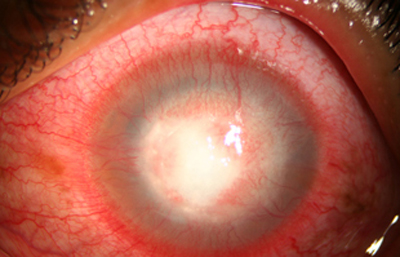

Superficie corneal irregular y grisácea, (Fig. 1, 2) con opácidades granulares en parche y formación de líneas epiteliales elevadas de aspecto granular (Fig. 3), que pueden arborizar dando imágenes de pseudodendritas. Opacidades superficiales satélites. (Figura 4) Inyección ciliar. Ulceración epitelial variante. (Figura 5).

Fig. 3 Líneas epiteliales elevadas. Síntomas de 40 días evolución